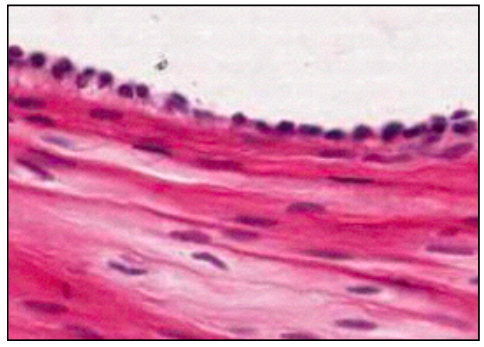

SIMPLE COLUMNAR

• height > width

• oval nucleus

• longer axis perp. to base of cell

• often microvilli or cilia at apical membrane

• GUT ENTEROCYTES and RESPIRATORY TRACT

left = gallballder